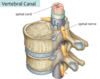

Vertebral Canal

A

- the channel through the center of the vertebral column

- formed by successful vertebral foramina“stacked” on top of one another

Vertebral Foramina

A

- the space located within the vertebra where the spinal cord passes through